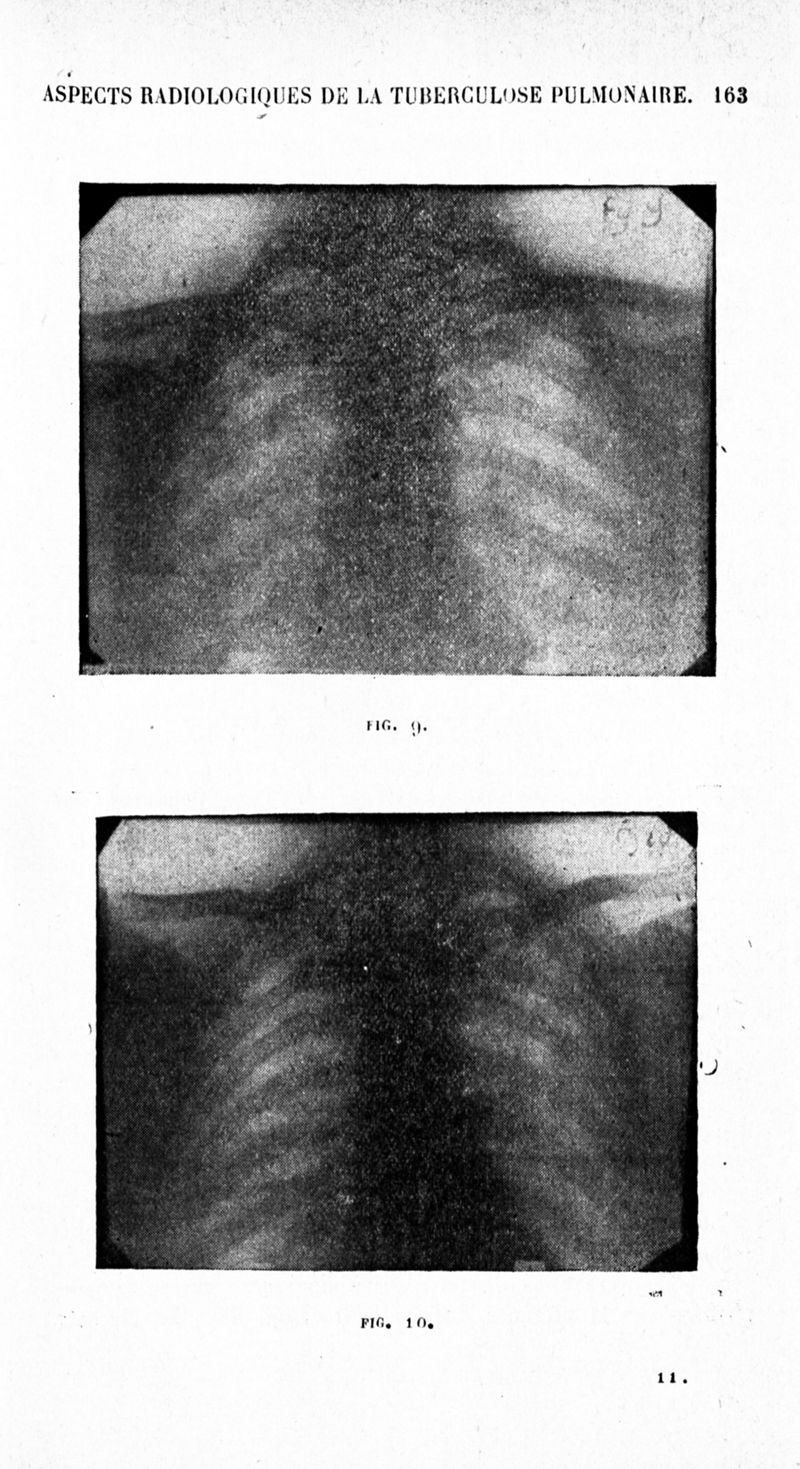

Archives de médecine et pharmacie navales

1936, n° 126. - Paris : Imprimerie nationale, 1936.